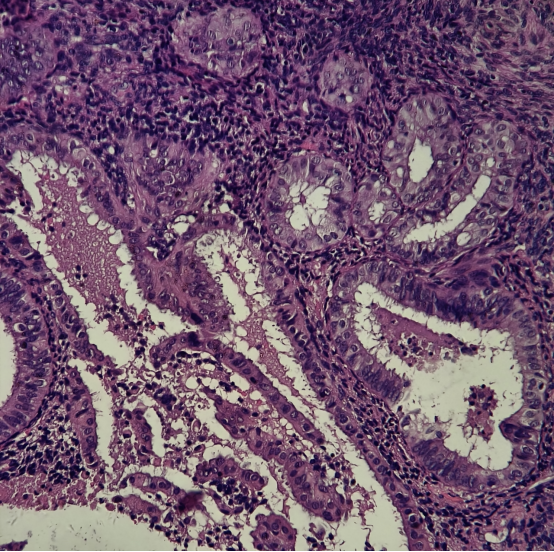

HE染色切片:

结果判读:组织中可见多灶性病变区域同时出现PTEN和PAX2的表达缺失。结合形态学改变,支持AH/EIN的诊断。